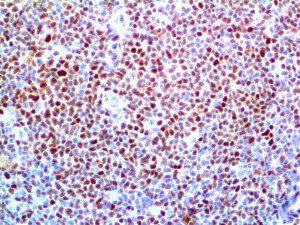

The first cytokines released are interleukin 1β (IL-1β) and tumor necrosis factor-α (TNF-α), which attract a variety of circulating white blood cells (WBCs) to the infection site, including neutrophils, monocytes, macrophages, and natural killer (NK) cells. This response, along with the antipathogenic chemicals released by these cells (i.e., complement), comprise the innate immune response. These cells directly attack the invading pathogen and also release additional cytokines, chief among them interleukin-1 and 6 (IL-6). IL-6 is essential for invoking the adaptive immune response, which calls T-cells, B-cells, and T helper (Th) cells to the infection site. IL-6 also stimulates further recruitment, proliferation and activation of macrophages.

It is the ICU physician who is most likely to witness one of the deadliest manifestations of the abnormal immunological response, the cytokine storm syndrome (CSS). This response is also referred to by some as the cytokine release syndrome (CRS). CSS is characterized by continuous activation and expansion of macrophage and lymphocyte populations, which secrete large amounts of cytokines, causing the cytokine storm. This massive cytokine release is akin to hemophagocytic lymphohistiocytosis (HLH) disease, a syndrome characterized by initial unchecked and persistent activation of cytotoxic T lymphocytes and NK cells.